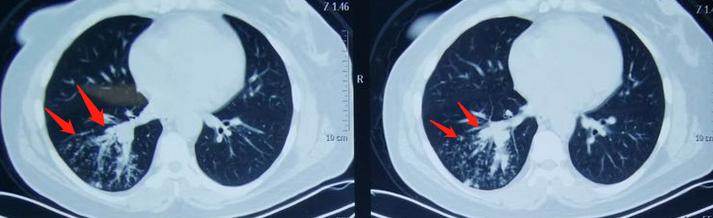

下图这位女士3个月前受凉感冒,反复咳嗽、咳痰,遇到冷空气时更严重,这期间到诊所输过两次液,时好时坏。

战战兢兢来医院做了肺部CT:

右下肺炎症,多发点片状影,支气管壁增厚,同时肺门去发现高密度影:

考虑支气管异物引发的阻塞性肺炎(病情迁延反复)。